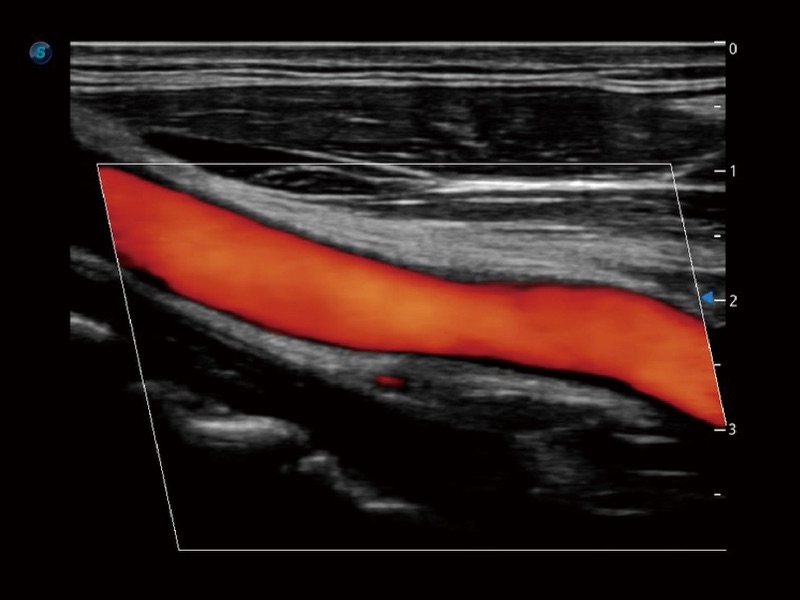

小器官应用

高分辨率血流成像技术提高了对低速血流信号的检测能力。在提高空间分辨率的同时,也克服了血流外溢现象,为用户提供更加真实的血流动力学信息。

血管内中膜的厚度值是预测心血管疾病风险的重要指标,Auto IMT可以实现血管近场和远场内中膜厚度的自动测量,为临床提供快捷有效的诊断工具。